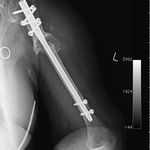

She was advised of the need to do some sort of stabilization which is necessary since the use of low-dose ultrasound has not helped in the healing process. She was unwilling to have any further operative intervention and sought further options. Eventually, she agreed to a fourth procedure of intra-medullary nail stabilization of the fracture and had this carried out in April 2011. An intramedullary nail was inserted in an antegrade manner and she has since gone on to heal the fracture site completely and has regained most of the function of the upper limb with no pain.